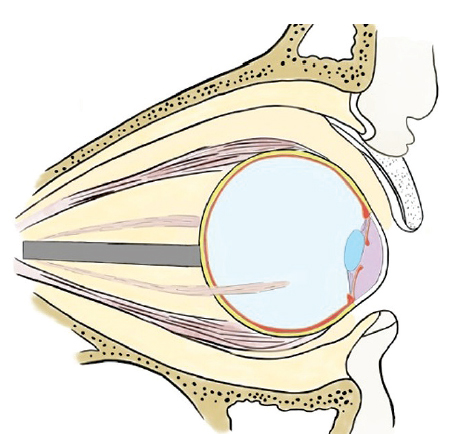

Fig. 11. Evisceration technique with removal of the cornea. Third stage: removal of the posterior pole of the sclera with neurectomy, installation of a spherical endoprosthesis

Рис. 11. Методика эвисцерации с удалением роговицы. Третий этап: удаление заднего полюса склеры с неврэктомией, установка сферического эндопротеза

Fig. 12. Evisceration technique with removal of the cornea with simultaneous formation of a supporting-motor stump and installation of an endoprosthesis. Stage four: installation of an external cosmetic prosthesis

Рис. 12. Методика эвисцерации с удалением роговицы с одномоментным формированием ОДК и установкой эндопротеза. Четвертый этап: установка наружного косметического протеза

Fig. 16. Installation of an external cosmetic prosthesis after globe removal using the evisceration method with removal of the cornea. The external cosmetic prosthesis is congruent with the surface of the endoprosthesis; there is no liquid or air vacuoles between them

Рис. 16. Установка наружного косметического протеза после удаления глазного яблока методом эвисцерации с удалением роговицы. Наружный косметический протез конгруэнтен поверхности эндопротеза, между ними отсутствует жидкость или вакуоли воздуха